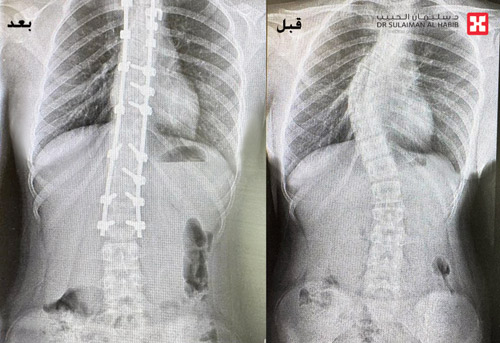

ذكر ذلك الدكتور واصف السباعي استشاري جراحة العظام والعمود الفقري رئيس الفريق المعالج. وأضاف بأنه فور وصول الفتاة لمركز طب وجراحة المخ والأعصاب والعمود الفقري بالعليا، تم إجراء الفحوصات لها وتبين أنها تعاني من آلام حادة ومتزايدة منذ 3 سنوات نتيجة لوجود اعوجاج شديد بالمنطقة الصدرية تبلغ زاويته (62) درجة في الجهة اليمنى بالعمود الفقري مع تحدب وتشوه بالقفص الصدري، وهو الأمر الذي سبب عدم استواء الكتفين أثناء المشي.

وأفاد الدكتور السباعي أن الفريق الطبي المعالج انتهى إلى ضرورة التدخل الجراحي العاجل لايقاف الانحراف المتزايد للعمود الفقري وتقويمه والحد من الأعراض والمضاعفات المتفاقمة، موضحاً أن الجراحة استغرقت 5 ساعات متواصلة تحت التخدير العام، وتم فيها استخدام تقنيات متطورة للمساعدة في تقويم الفقرات وتعديلها بالإضافة إلى جهاز المراقبة العصبية، وقد تمكن الفريق الطبي بفضل الله من تقويم العمود الفقري بنسبة 96%، علاوة على تثبيت ودمج الفقرات بشكل ممتاز.